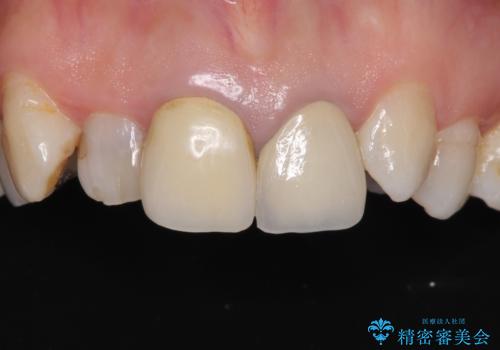

矯正治療後にはオールセラミッククラウンにて補綴治療を行うこととしました。

歯冠長延長術を行ったことで、自然な形態かつ清掃性の高いセラミッククラウンを装着することができました。